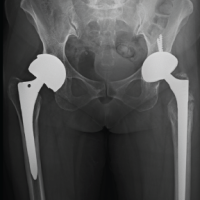

A 45-year-old gentleman sustained a Gustilo-Anderson 3B open right calcaneal intra-articular fracture after a fall from height of approximately 3 m. There were no other bony injuries besides the calcaneal fracture. The calcaneal fracture was initially stabilized with a joint spanning external fixator while the patient underwent multiple surgeries for wound debridement. K-wires were used to reconstruct the subtalar joint, and a cement spacer was utilized to fill the significant bone void (Fig. 1 and 2). Twenty days after the initial injury, the large skin defect was covered using a contralateral anterolateral thigh flap. The external fixator was converted to an Ilizarov circular frame 1 month after soft-tissue reconstruction surgery. Approximately 10 weeks after the initial injury, a biodegradable PCL-TCP synthetic bone scaffold (Osteopore®) was utilized to fill the critical-sized bone defect encapsulated by a pseudomembrane formed by the cement spacer from earlier surgeries (Fig. 3). The scaffold was a custom 3D-printed cuboid-shaped block measuring approximately 8 × 4 × 4 cm which was further cut to fit the exact bony defect. The approximate size of the scaffold needed was based on estimates of the size of the bone defect from pre-operative computed tomography (CT) scans. Autogenous bone graft and bone marrow aspirate concentrate (BMAC) was harvested from the ipsilateral iliac crest and packed into the porous scaffold (Fig. 4). A 6.5 mm cancellous screw was inserted, from the posterior calcaneal tuberosity through the subtalar joint into the talus, to anchor the scaffold (Fig. 5). The Ilizarov circular frame was removed 3 months later. Subsequently, the patient underwent elective removal of the right calcaneal screw and liposuction-assisted debulking of right foot flap 1 year postoperatively.